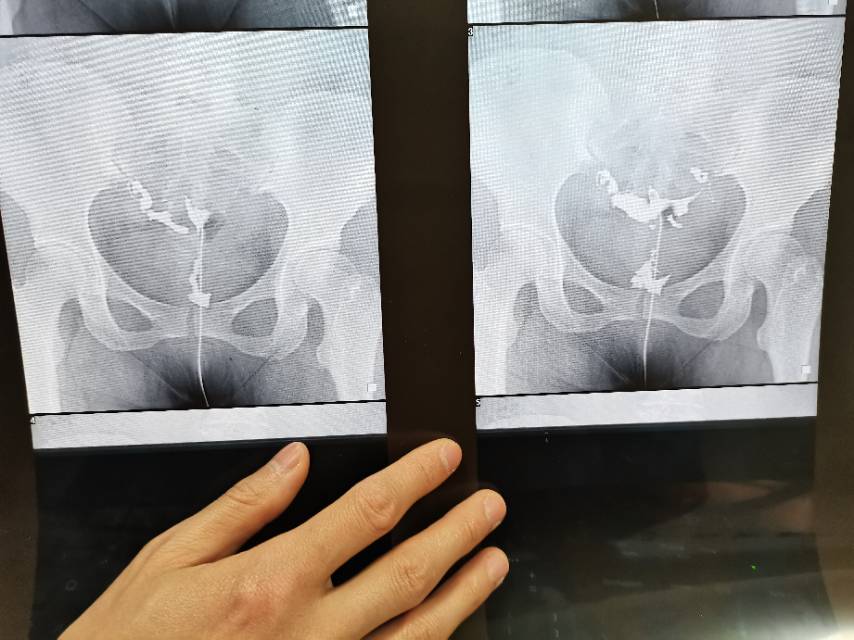

医生您好麻烦看下我的输卵管造影片影像科的报告